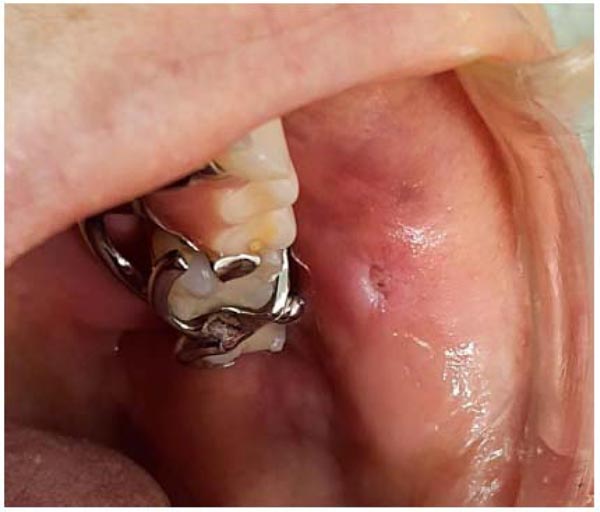

Clinically, the patient presented an asymptomatic, white-pink colored increase in volume in the jugal mucosa, measuring approximately 0.5 cm. On palpation, the lesion was soft and resilient. Based on these clinical characteristics and history, Papilloma was the initial clinical diagnosis of the lesion (Fig. 1).

A high-intensity diode laser with a wavelength of 980 nm (Thera Lase Surgery DMC, São Carlos, Brazil) was used in a contact-mode technique under local anesthesia. Irradiation was delivered using a handpiece connected to a single-use fiber (300 μm in diameter) that was set for use in continuous-wave mode, at a power output of 1.5, for excising the lesion. The diode laser provided an optimum combination of clean cutting of the tissue and hemostasis (Fig. 2). The excised tissue was sent for histopathological study to confirm the clinical diagnosis (Fig. 3).